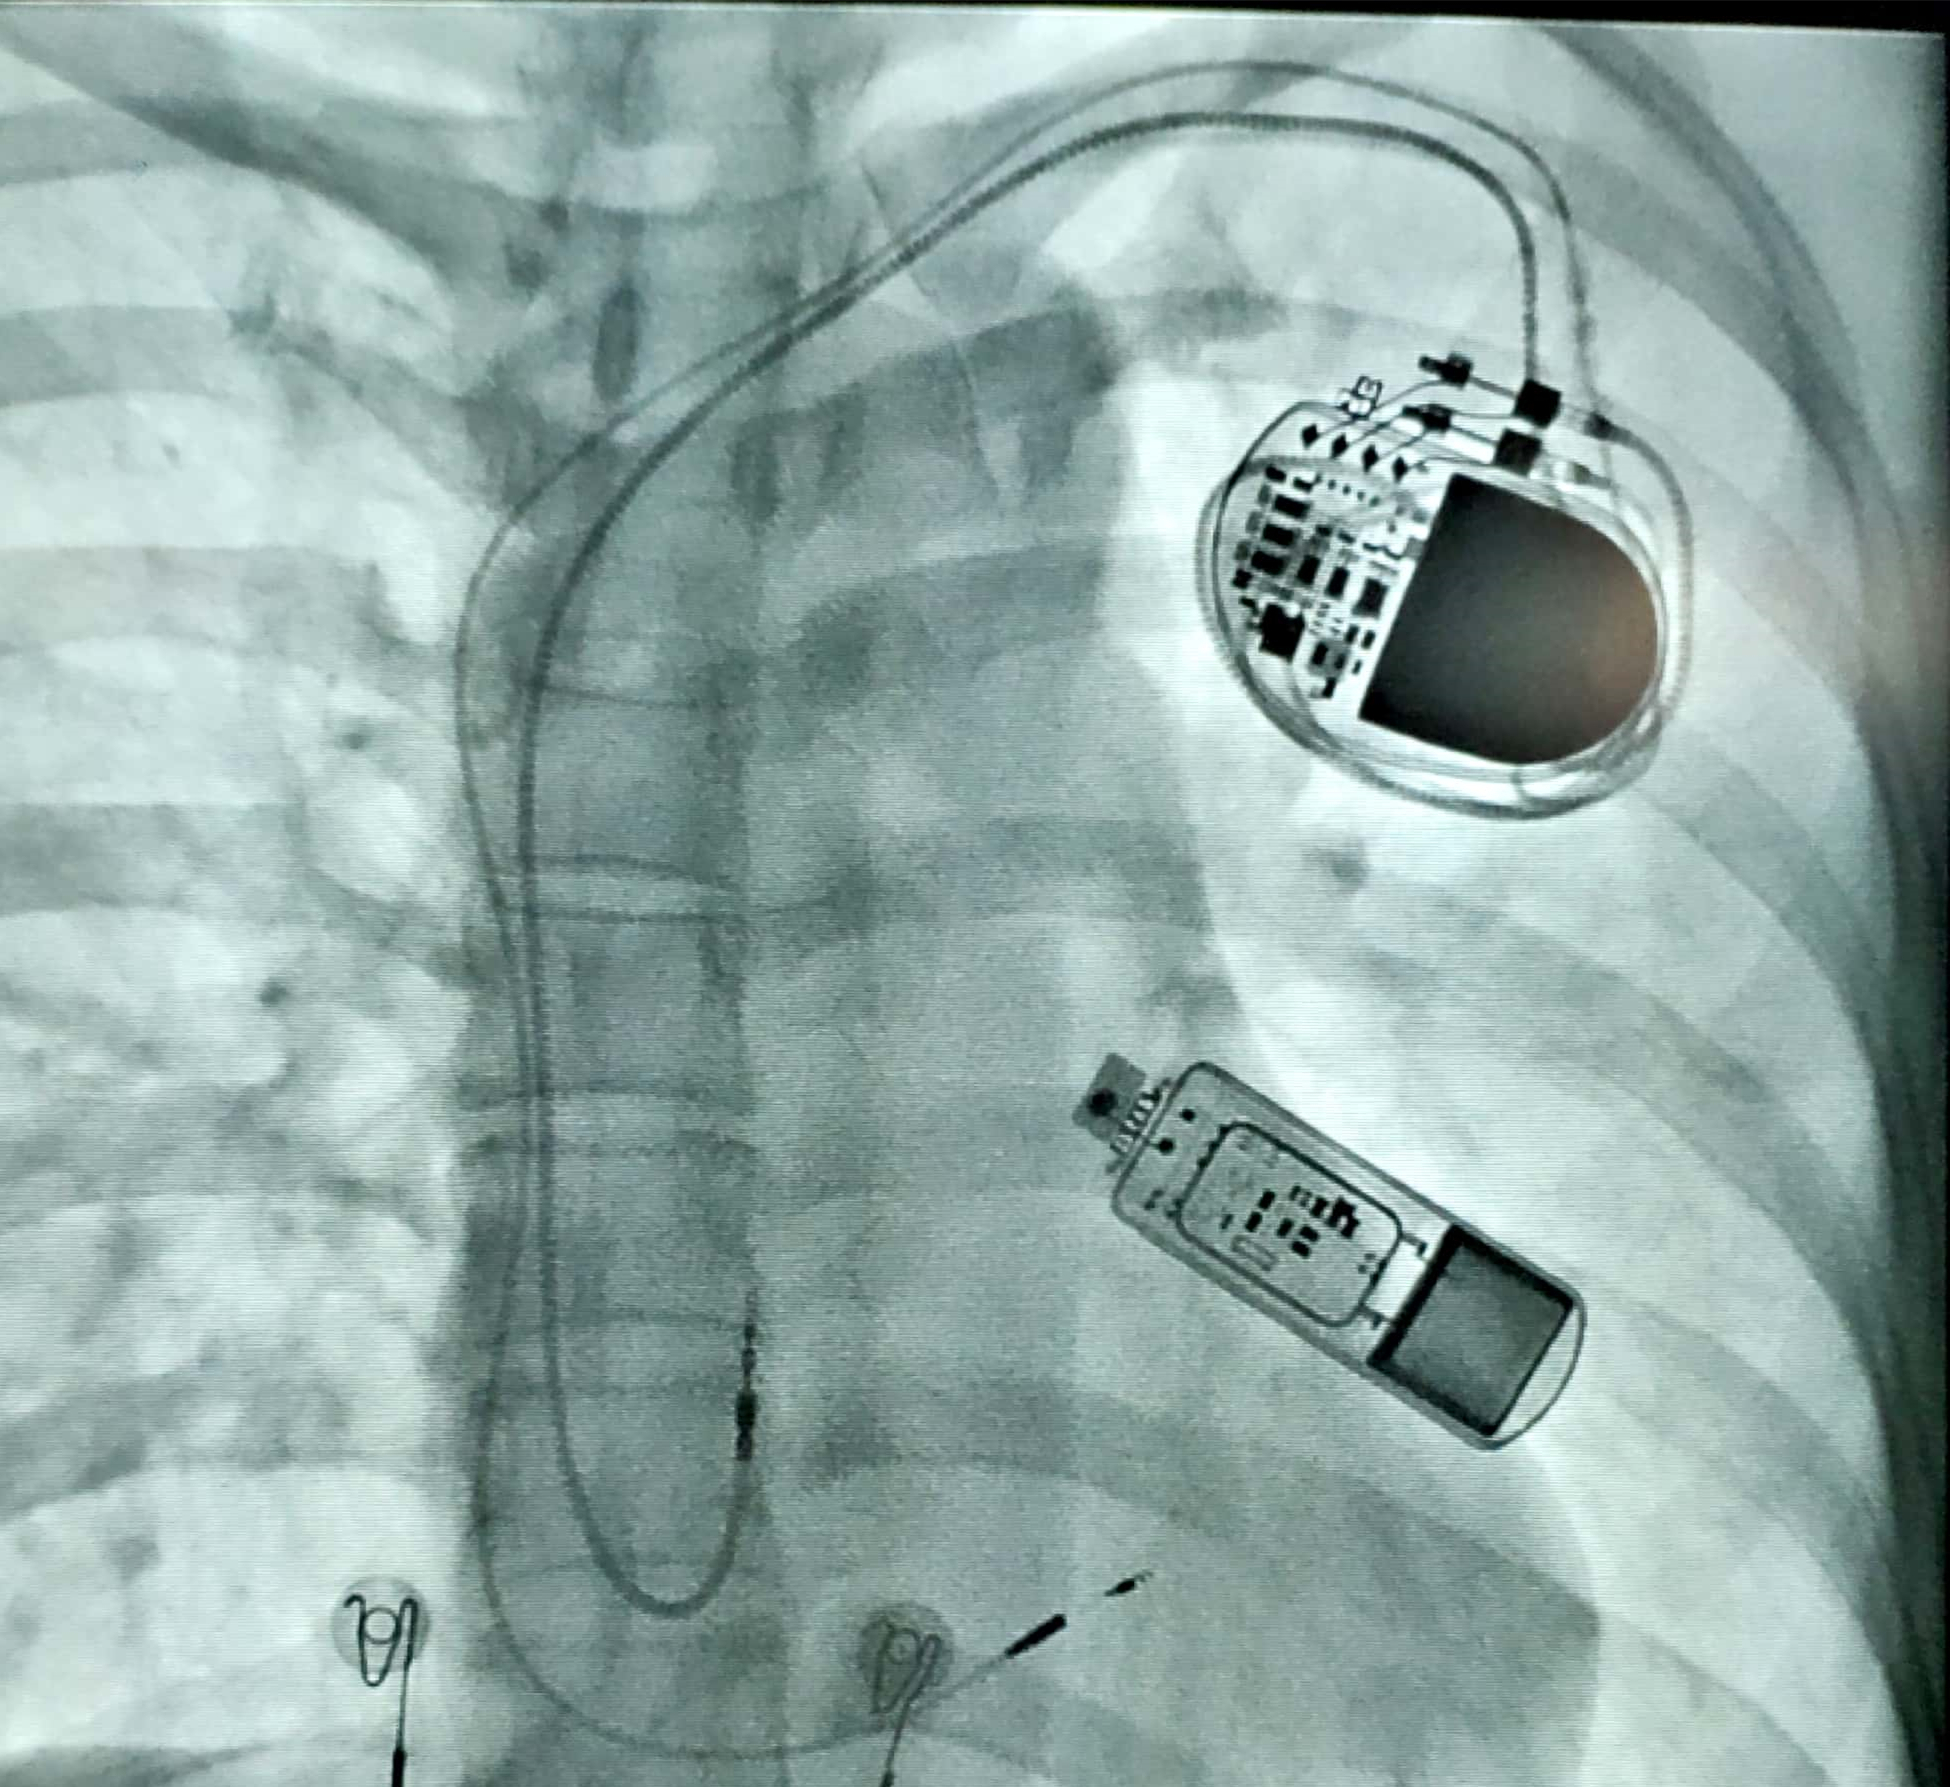

结果就在4月,吴阿姨去而复返,一而再、再而三的头晕、晕厥让她下定决心,要解决这个大“心病”。经充分准备,医院电生理团队在她左胸心前区切开仅2cm的小口,十多分钟后就将一片口香糖大小的心电事件记录仪成功置入皮下,手术操作简单、创伤小,患者几乎感觉不到痛苦。

这枚心电“U盘”很快发挥了作用。近日,吴阿姨又一次晕厥发作后就诊,医生当即利用体外无线连接,调取仪器数据进行分析,这次记录仪终于抓取到了她发病时的心电图,显示在她晕厥期间,心脏窦性停搏约10秒,而后心率才逐渐恢复。这下证据确凿,若任其发展,很有可能导致患者猝死,电生理团队当即对症为其植入了心脏起搏器,一举解除了吴阿姨十多年的心头大患,让她终于得以“安心”生活。